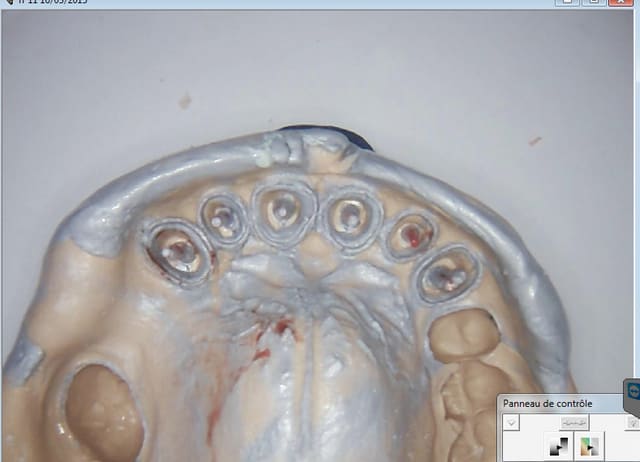

Il manquait 3mm au niveau des incisives. Ca va mieux non ( provisoires auto moulage du wax up en place) ?

Capture d e cran 2015 03 16 12.29 - Eugenol

Capture d e cran 2015 03 16 12.32 - Eugenol

Capture d e cran 2015 03 16 12.35 - Eugenol